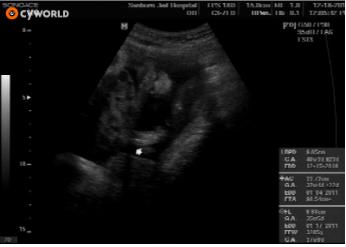

<36주차>통통한우리효자-

12.18 우리효자가 36주4일되던날- 이제 엄마,아빠랑 만날날이 ...